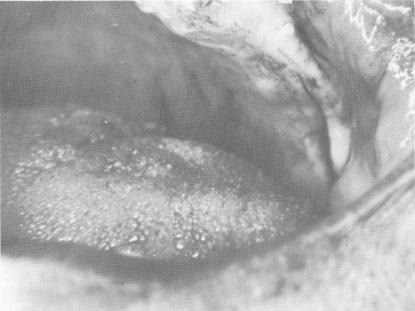

Fig. 15-44. An incision was made along the fibromucosal tissue at the crest of the ridge.

4 Incision along fibromucosal tissue at crest of  maxillary ridge